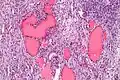

Higher magnification

Higher magnification